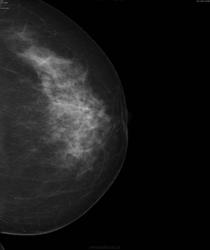

Предлогаю похожий случай. Пациентке 59лет.

да не было в июне.., поэтому и спорят об целесообразности скрининговой маммографии. а во втором случае могу только предположить что справа...

Видимо во втором случае пропуск.

А в каком месте опухоль во втором случае? В прямой проекции правой м.ж. тень хорошо видна, а в косой ее же не смогла найти)

зы все, нашла

Думаю, что здесь.